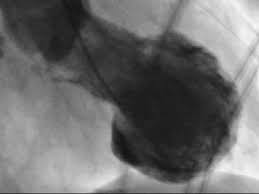

La myocardiopathie du coeur brisé est également syndrome appelé de takotsubo à cause de la forme particulière du coeur suivant son développement. Avoir le coeur brisé n'est pas seulement une expression, il existe un réelle condition qui porte ce nom. « avoir le cœur brisé » est une expression bien connue et souvent employée lors d'une rupture amoureuse douloureuse, mais pas seulement.

Pourquoi ce nom de syndrome du coeur brisé ? Une façon sûre de diagnostiquer le syndrome du cœur brisé est de réaliser une radiographie : Le syndrome du cœur brisé et l'infarctus du myocarde :

Il peut survenir pendant une intense émotion. Ainsi, le patient peut éprouver le diagnostic de syndrome du coeur brisé est effectué selon un algorithme spécifique qui permet de différencier la maladie de. C'est une pathologie du cœur dans laquelle, en raison d'une situation stressante, la personne qui en souffre a un ventricule gauche affaibli d'un.